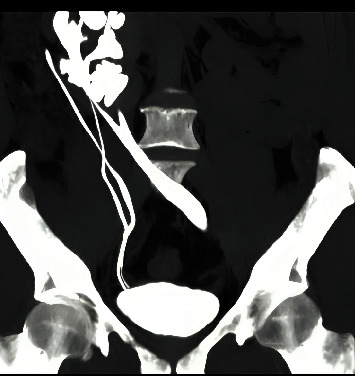

Crossed-fused renal ectopia (CFRE) is a rare congenital anomaly where both kidneys are fused on the same side. We report a case of a 52-year-old male patient who presented with central abdominal pain associated with hematuria and dysuria, with a history of left open ureterolithotomy. Abdominal computed tomography (CT) showed an 18-mm left distal ureteric stone and a CFRE with a bilateral duplex-collecting system. Left ureteroscopy and laser lithotripsy with magnetic double-J stent insertion were carried out successfully, and the patient was discharged on the same day in fair general condition.

Abstract Image